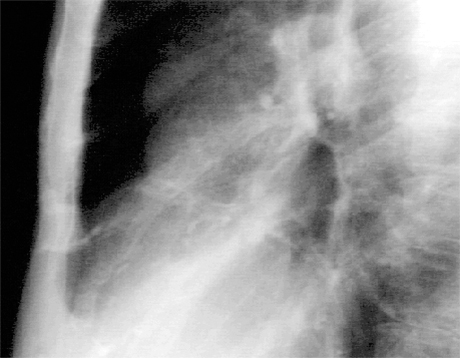

This chest X ray shows calcified coronary arteries. The lateral view is often best for demonstrating calcium in the coronary vessels. Calcifications are much more common in the proximal parts of the vessel, usually within two centimeters of the root of the aorta and reflect coronary atherosclerosis.

In this enlargement of the lateral view, the railroad track shadows of calcium are more easily seen. There is proximal calcification of some of the branches of the main vessel.